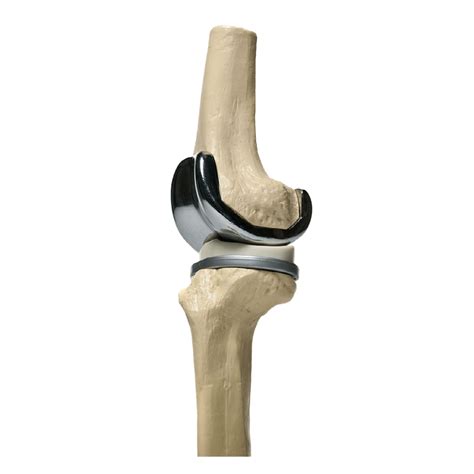

La prótesis de rodilla es un implante quirúrgico diseñado para sustituir las superficies articulares dañadas de la articulación de la rodilla, generalmente a causa de una osteoartritis avanzada, artritis reumatoide o una lesión grave. El objetivo principal es reducir el dolor causado por el desgaste del cartílago y mejorar la alineación y el funcionamiento de la articulación.

El dispositivo protésico consta generalmente de tres componentes principales:

• Componente femoral: Fabricado de aleaciones metálicas duraderas (como cobalto-cromo), reemplaza la parte inferior del fémur.

• Componente tibial: Generalmente de titanio o aleación de cobalto-cromo, reemplaza la parte superior de la tibia.

• Inserto de polietileno: Una pieza de plástico de grado médico de alta resistencia que actúa como cartílago artificial, permitiendo que el metal se deslice suavemente sobre el componente tibial.

Este reemplazo articular no solo alivia el dolor, sino que también corrige deformidades como el genu varo (rodillas en paréntesis) o el genu valgo (rodillas en forma de X), mejorando la estabilidad general del paciente.